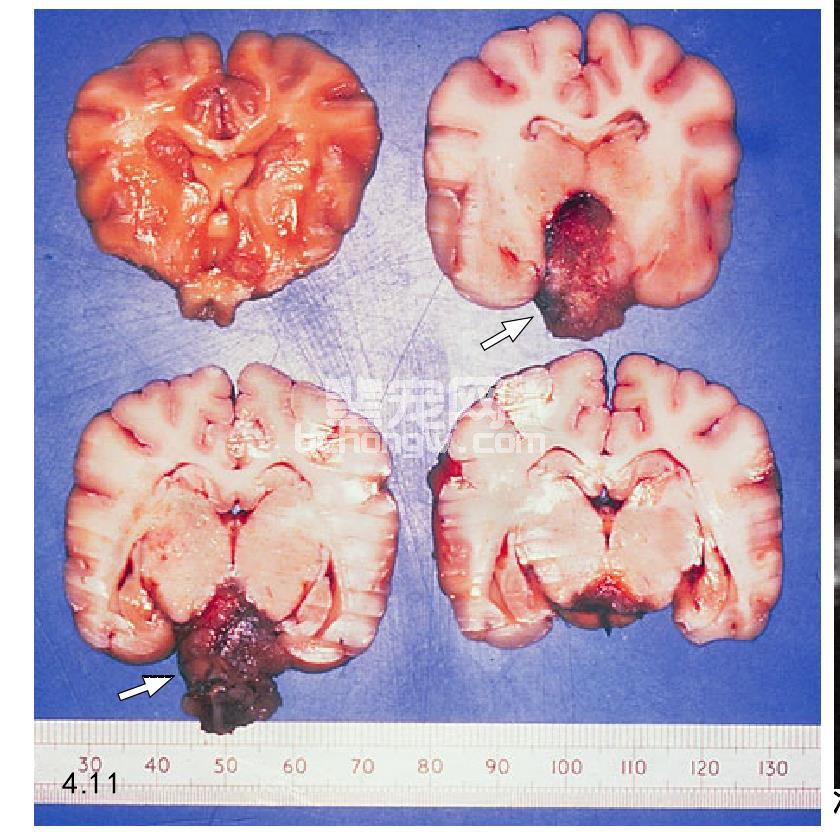

图4.11 垂体肿瘤的剖检样品(箭头所指)。